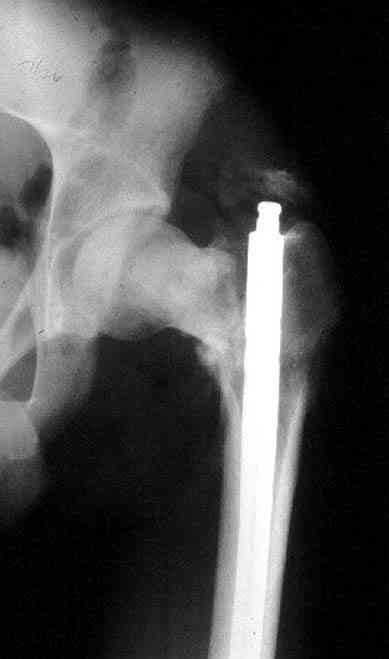

Уважаемые коллеги. Благодарим за дискуссию. Мы решили выполнить комбинированную операцию - эндопротезирование тазобедренного сустава и ретроградный интрамедуллярный остеосинтез (одномоментно)